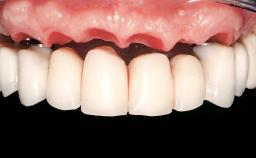

Immediate Loading of Six Implants in the Mandible and Six Implants in the Maxilla and Final Restoration with Full-Arch CAD/CAM Metal Framework FDPs Involving Digital Planning and Guided Surgery

Prosthesis Type FDP